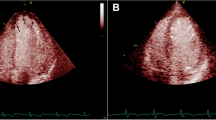

Cardiac function estimated by EF was not different between the two groups at 24 h (40.66 ± 1.58% versus 39.87 ± 3.10%, p = 0.242) or 1 month (41.16 ± 2.12% versus 40.52 ± 2.76%, p = 0.342). However, the EF value in the low IMR group was significantly higher than that in the high IMR group at 3 months (43.06 ± 2.63% versus 40.20 ± 2.67%, p < 0.001) and 1 year (44.16 ± 2.40% versus 40.13 ± 3.48%, p < 0.001) after PCI (Table 3 and Fig. 2).

IMR had no significant correlation with left ventricular ejection fraction (LVEF) at 24 h (r = − 0.0425, p = 0.1490) and 1 month (r = − 0.0542, p = 0.0651) but had a negative correlation with LVEF at 3 months (r = − 0.1014, p = 0.0040) and 1 year (r = − 0.1754, p < 0.0001) (Fig. 3).